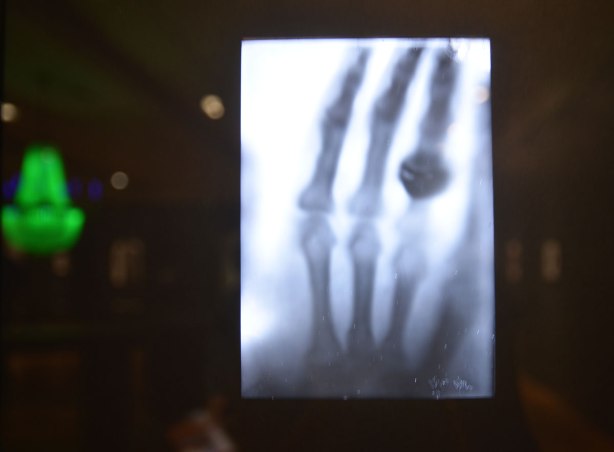

below: The first photograph of the bones of the hand, by Wilhelm Rontgen in 1895. Rontgen was a German physicist who discovered x-rays (or Rontgen rays) in 1895 and he produced this image of his wife’s hand shortly after. The green in the picture below is a reflection of the chandelier that the AGO has hanging in the room where this exhibit is being shown.